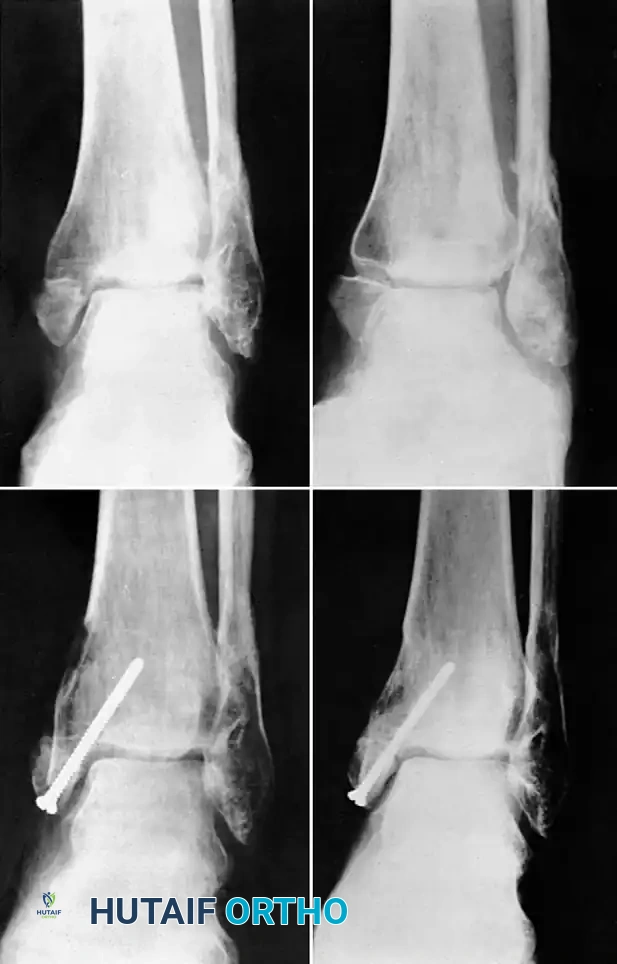

Medial Malleolus

A fracture of the medial malleolus occasionally fails to unite, especially after nonoperative (closed) treatment where periosteum or the deltoid ligament may interpose between the fracture fragments.

Surgery may be indicated for the few nonunions in which other serious complications of the fracture, such as advanced traumatic arthritis, are not seen on radiographs, and ideally if the injury is less than 2 years old. The standard surgical technique usually includes excision of the fibrous nonunion, application of autogenous bone grafts, and rigid internal fixation of the malleolar fragment.

Technique 56-7: Sliding Graft for Medial Malleolus

- Exposure: Expose the nonunion through an anteromedial curved incision 10 cm long.

- Preparation: Reflect the periosteum anteriorly and posteriorly. Meticulously remove all interposed fibrous tissue from the nonunion site. Freshen the ends of the fragments using a curette or high-speed burr, but remove no bone from their deeper (articular) edges to avoid joint penetration. Carefully hollow out the distal fragment to receive the graft.

- Graft Harvest: Beginning at the nonunion and using an oscillating motor saw, harvest a cortical graft approximately 4 cm long and 1 cm wide from the proximal tibial fragment.

- Graft Placement: Displace (slide) the graft distally across the nonunion site and into the prepared trough in the distal fragment.

- Fixation: Hold the distal fragment in its precise anatomic position, restoring the mortise. Transfix the fragments and the sliding graft with a fully threaded or partially threaded 4.0 mm cancellous lag screw.

- Augmentation: Place cancellous bone chips (harvested from the proximal metaphysis) around the graft site to enhance osteoconduction.

- Closure: Confirm the position of the graft, the screw, and the joint space with intraoperative fluoroscopy. Close the wound in layers.

Fig. 56-18 Nonunion of medial malleolus treated by sliding graft.

Postoperative Protocol: A non-weight-bearing cast is applied from the toes to just distal to the knee. At 2 weeks, sutures are removed, and a walking cast or rigid boot is applied. Partial weight-bearing is allowed during the next 2 weeks, advancing to full weight-bearing thereafter. The immobilization is discarded when radiographs confirm osseous union, typically at 8 to 10 weeks.